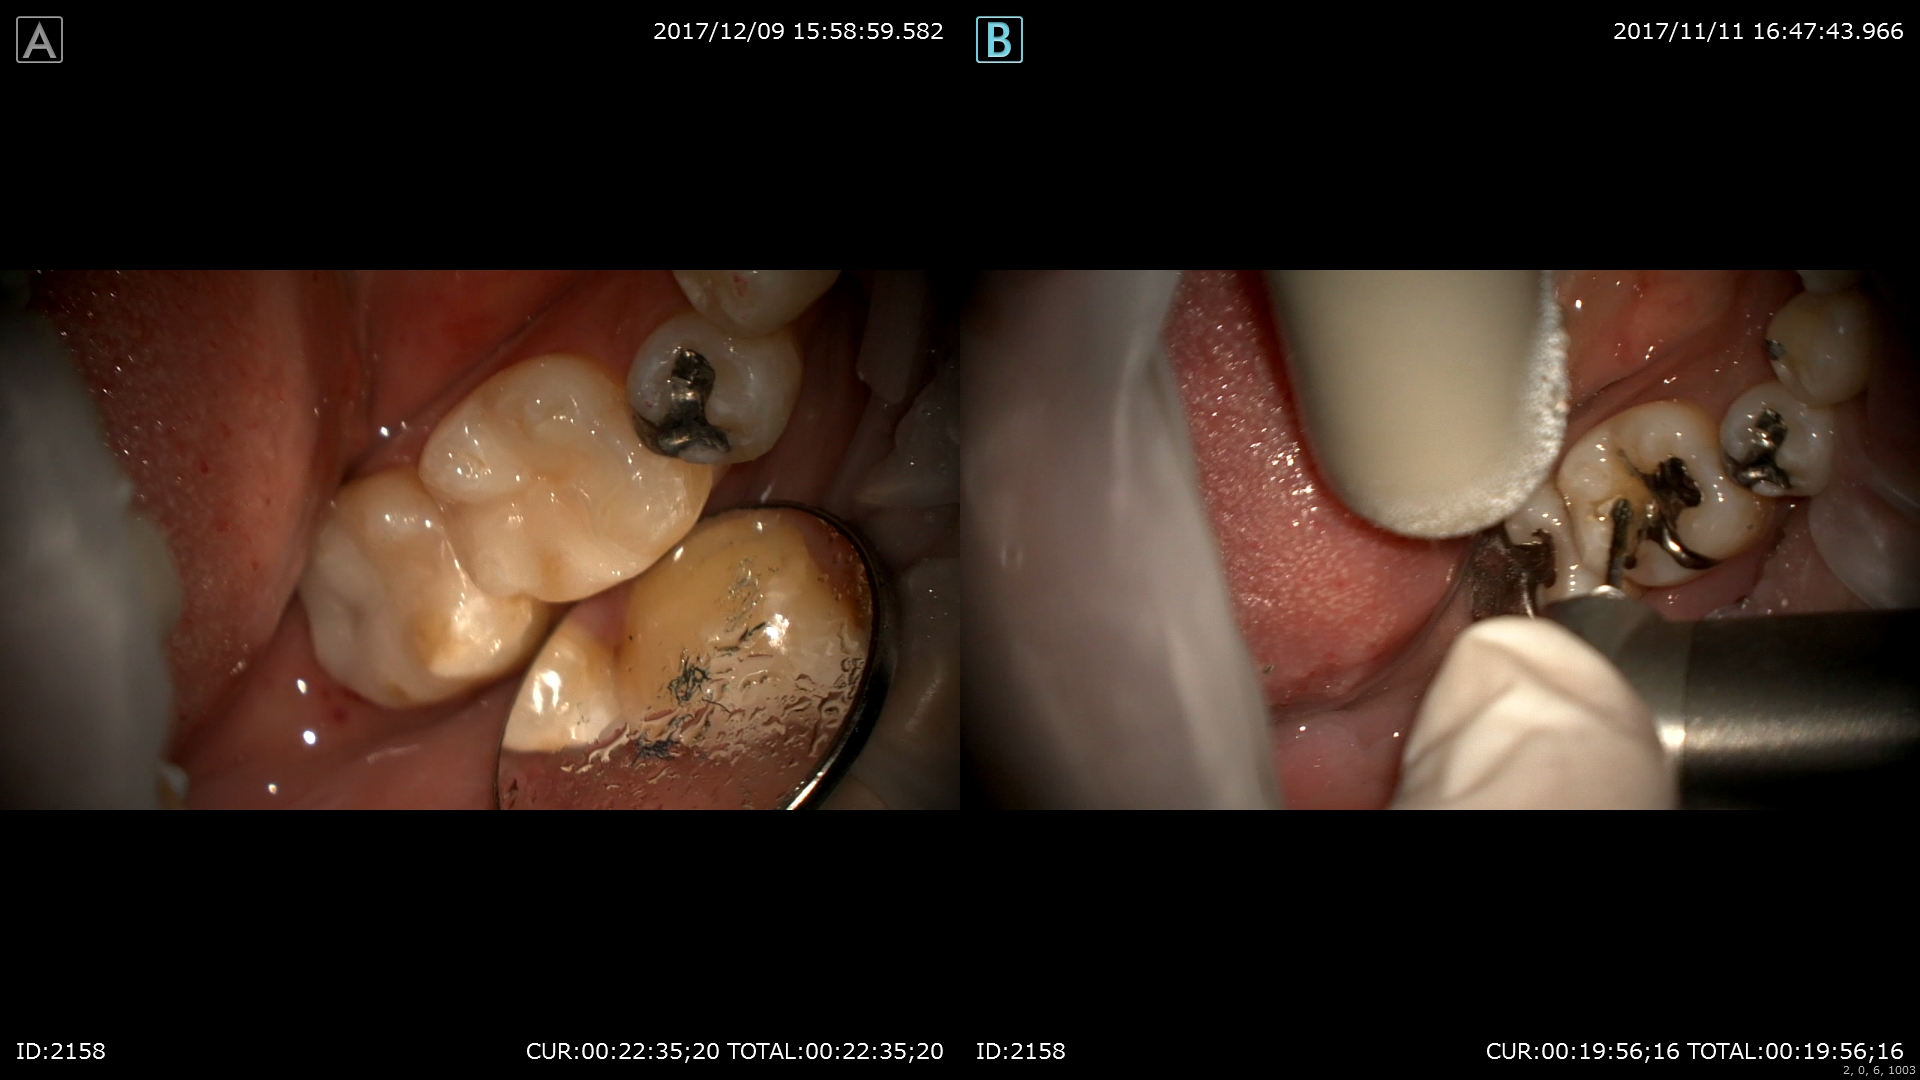

最後はセラミック治療

術前右。術後左。金属を使用しない治療は体に良いと証明されています。

かみ合わせも確認。

患者さまも金属がとれて喜んでいました。僕も幸せ!